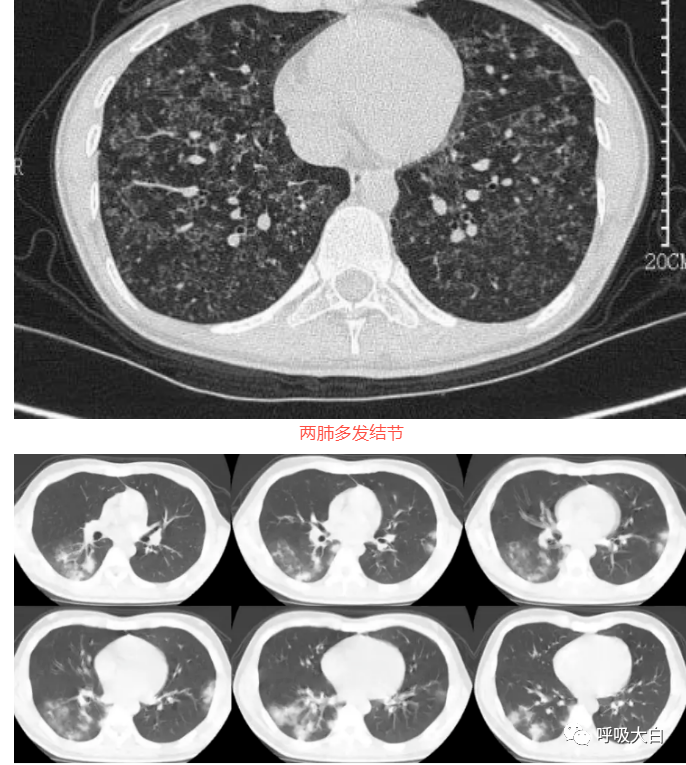

晕征是指肺部CT上表现为围绕结节或肿块周围的略低于肿块密度而又高于肺实质密度的环形磨玻璃影。晕征最早用于描述局灶性侵袭性曲霉菌病灶周围出血的征象,被认为是肺部真菌感染的特异性影像表现。晕征中磨玻璃样影通常和结节出血相关,这些结节出血的机制包括:出血性梗死、血管炎、支气管动脉瘘以及坏死等。当然了,磨玻璃影还可以由肿瘤或炎症浸润周围肺组织造成。

肺隐球菌病:下图。肺隐球菌病的影像学表现多种多样,缺乏尤特异性。免疫功能正常者常使病灶局限形成肉芽肿结节,因此胸部 CT常见表现为单发或多发的结节肿块影,直径大小不等,边界清楚,可有分叶及毛刺,容易误诊为肺癌和肺转移瘤。其次还可表现为斑片浸润影、实变影和偏心后壁空洞。病灶多位于中下肺野外带分布,可伴有支气管充气征、晕征 。